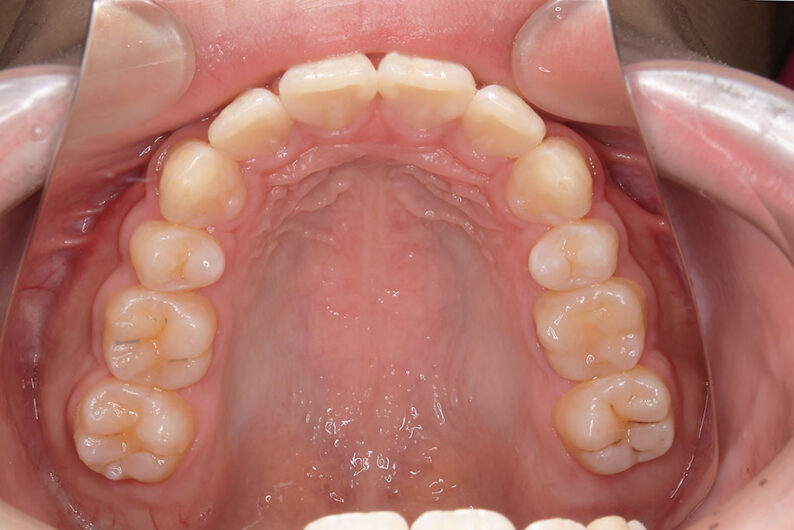

歯が重なっている、出っ歯を治したい 以前に治療した方からの紹介で来院した患者さんです。 上下顎前歯部の叢生(がたつき)、上下顎前歯の前方傾斜、 骨格的上顎前突傾向でした。 小児矯正で叢生の緩和を行い、 本格矯正で前方傾斜した前歯の改善を行いました。 マルチブラケット 動的治療期間 3年3か月 調整回数25回

平均来院間隔1.5か月に1度の来院でした。 治療後は後戻りの軽減するために、親知らず(第三大臼歯)の抜歯をお勧めしています。